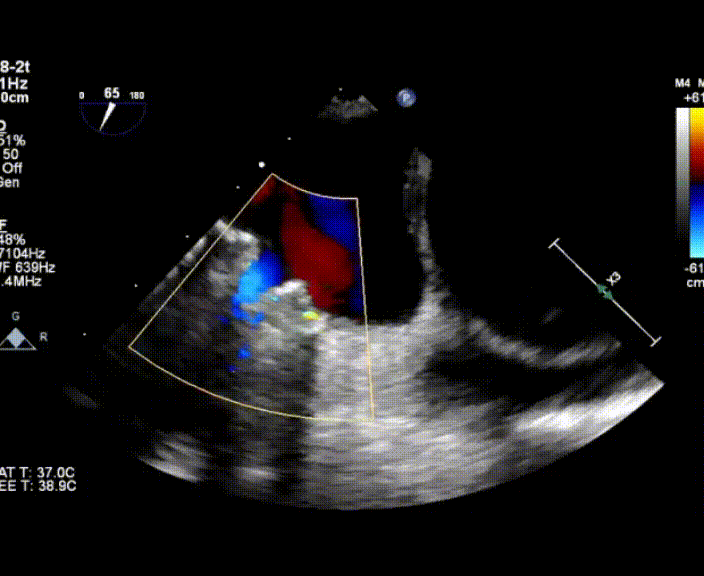

術中首先在局麻下穿刺股動脈、股靜脈,完成心導管檢查評估后轉為全麻,在食道超聲引導下穿刺房間隔,穿刺成功后將加硬導絲送入左上肺靜脈建立軌道,根據患者病情行球囊預擴張后植入6mm孔徑房間隔造孔支架,經透視及食道超聲評估支架左右盤展開良好,夾持于房間隔兩側,固定穩定、位置良好,食道彩超顯示房水平右向左為主分流,分流孔直徑符合預期大小,心導管檢查評估達到預期效果,釋放造孔支架。術后12h患者下床活動,恢復順利,擬于近日完善術后評估后出院。